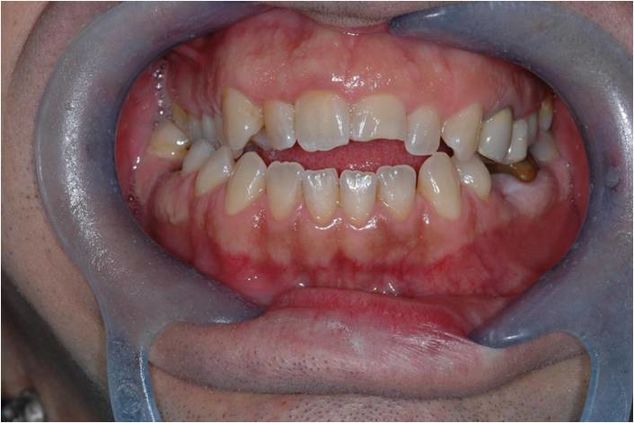

The patient has a posterior unilateral crossbite and an anterior openbite.[18] The crossbite is another disturbing element of the normal occlusion[19] for which it is compulsorily treated together with the openbite.[20][21] This type of reasoning means that the model (masticatory system) is 'normalized to occlusion'; and read in reverse, it means that the occlusal discrepancy is the cause of malocclusion, hence, a disease of the Masticatory System, and therefore an intervention to restore the physiological masticatory function is justifiable. (Figure 1a).